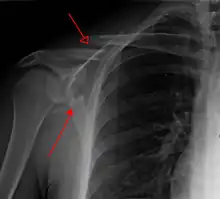

Diagnosis

Most fractures of the scapula can be seen on a chest X-ray; however, they may be missed during examination of the film.[1] Serious associated injuries may distract from the scapular injury,[4] and diagnosis is often delayed.[3] Computed tomography may also be used.[1] Scapular fractures can be detected in the standard chest and shoulder radiographs that are given to patients who have had significant physical trauma, but much of the scapula is hidden by the ribs on standard chest X-rays.[4] Therefore, if scapular injury is suspected, more specific images of the scapular area can be taken.[4]